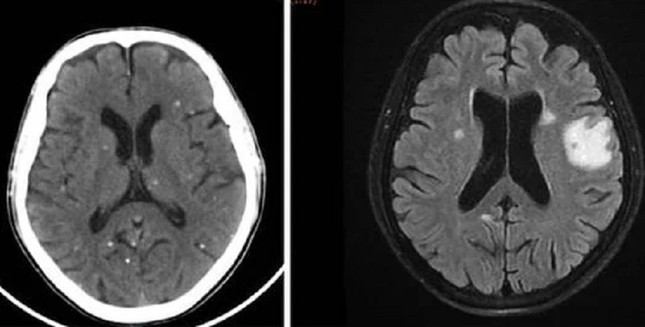

Nang sán dải ký sinh ở bán cầu não hai bên là nguyên nhân khiến người bệnh bị tổn thương não, biểu hiện như đột quỵ

TS.BS Trần Thanh Hùng, Phó khoa Nội Thần kinh Tổng quát, Bệnh viện Nhân Dân 115 cho biết, qua thăm khám và chẩn đoán hình ảnh ghi nhận, người bệnh có tổn thương não nhiều vị trí, phù não. Kết quả xét nghiệm huyết thanh học cho thấy, bệnh nhân dương tính với ấu trùng sán dải lợn (Cysticercus).

Trên kết quả X-quang và CT-Scan toàn thân, bác sĩ phát hiện bệnh nhân có vô số nang sán dải còn sống hoặc đã bị vôi hóa ở não, nhu mô phổi, trong da, cơ trên toàn bộ cơ thể. Qua điều tra dịch tễ, bác sĩ ghi nhận bệnh nhân có thói quen hay ăn gỏi thịt lợn tái sống và uống nước không đun sôi trong nhiều năm.

Bệnh nang sán dải lợn có thể gây ra nhiều triệu chứng thần kinh nghiêm trọng như co giật, đau đầu kéo dài, rối loạn ý thức. Do đó, việc chẩn đoán sớm và chính xác đóng vai trò quan trọng trong điều trị và phòng ngừa các biến chứng nguy hiểm.